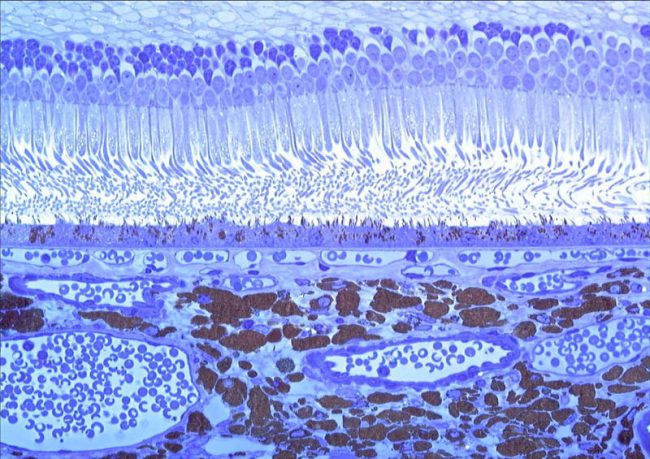

- Photoreceptor toxicity assessment

- Retinal Pigment Epithelium (RPE) toxicity assessment

- Photoreceptor toxicity assessment

- Retinal Pigment Epithelium (RPE) toxicity assessment